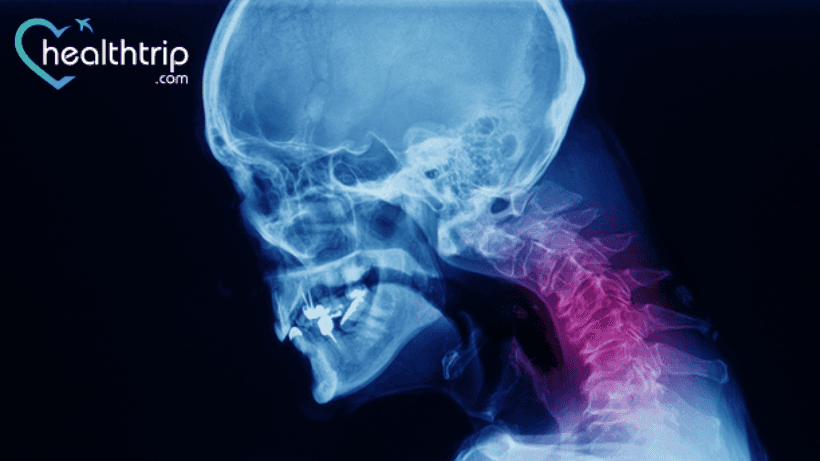

Ang bawat isaang operasyon o pamamaraan ay nagdadala ng ilang mga panganib at komplikasyon. Ngunit, kahit na mababa ang panganib para sa ilang mga operasyon, hindi mo dapat palampasin ang maliliit na pagkakataong magkaroon ng malubhang komplikasyon. Dito napag-usapan natin ang mga komplikasyon ng anterior cervical discectomy at fusion surgery. Panatilihin ang pagbabasa upang malaman ang parehong.

Bakit kailangan mong sumailalim sa ACDF surgery?

Ang anterior cervical discectomy at fusion ay karaniwang inirerekomenda para sa mga pasyente na may cervical spondylosis o disc herniation na may myelopathy/radiculopathy na

hindi tumutugon sa konserbatibong therapy. Bilang karagdagan, maaari itong ipahiwatig sa ilang malignant, traumatic, o nakakahawang proseso ng cervical vertebrae na nagdudulot ng kawalang -tatag.

Paano ginagawa ang ACDF surgery?

Ang pamamaraan ay isinasagawa sa pamamagitan ng isang anterolateral neck incision, na may surgical approach na dumadaan sa medially sa pagitan ng aerodigestive tract (trachea, esophagus, pharyngeal muscles) at laterally sa pagitan ng carotid neurovascular bundle (carotid artery, internal jugular vein, vagus nerve).

Ang intervertebral disc at ang fibrocartilage na sumasaklaw sa katabing vertebral endplates ay aalisin (upang payagan ang tuluyang osseous fusion). Ang pag -abot pabalik sa posterior longitudinal ligament, pag -alis ng mga osteophyte at disc protrusions pati na rin ang pagpapalawak sa paglaon upang mabulok ang neural exit foramina, ay posible.

Kasunod ng decompression, ang isang interbody spacer ng ilang uri ay ipinakilala upang tulungan ang pagsasanib/pagbutihin ang katatagan.

Pagkatapos nito, karaniwang ginagamit ang isang anterior cervical plate na may mga turnilyo na pumapasok sa mga vertebral na katawan sa itaas at ibaba ng operative segment upang magbigay ng karagdagang katatagan..